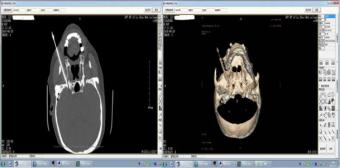

CT引导下神经射频治疗

其精准的导航系统能够把身体内突出部位的髓核变性、凝固,收缩减小体积,解除压迫,用来治疗腰椎间盘突出、颈椎病和神经疼痛等病症均有不错的疗效。